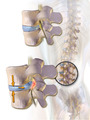

When a tear in the outer, fibrous ring of an intervertebral disc allows the soft, central portion to bulge out beyond the damaged outer rings, the disc is said to be herniated.

Disc herniation is frequently associated with age-related degeneration of the outer ring, known as the annulus fibrosus, but is normally triggered by trauma or straining by lifting or twisting. Tears are almost always postero-lateral (on the back of the sides) owing to the presence of the posterior longitudinal ligament in the spinal canal.[1] A tear in the disc ring may result in the release of chemicals causing inflammation, which can result in severe pain even in the absence of nerve root compression.

Disc herniation is normally a further development of a previously existing disc protrusion, in which the outermost layers of the annulus fibrosus are still intact, but can bulge when the disc is under pressure. In contrast to a herniation, none of the central portion escapes beyond the outer layers. Most minor herniations heal within several weeks. Anti-inflammatory treatments for pain associated with disc herniation, protrusion, bulge, or disc tear are generally effective. Severe herniations may not heal of their own accord and may require surgery.